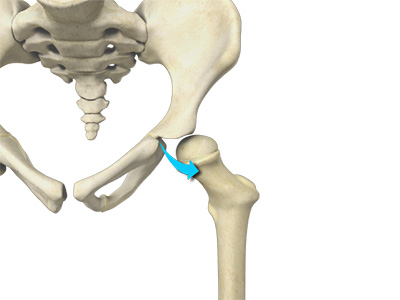

Hip dysplasia is a medical condition where the acetabulum (hip socket) does not fully cover the ball-like head at the top of the femur (thighbone). Most people who have hip dysplasia are born with it.

Your hip is a ball-and-socket joint where the ball of your thigh bone (femoral head) fully fits into the socket of the hip bone (pelvis) to form the hip joint. At birth, your hip joint is made of soft cartilage that later hardens into bone. Over time, the ball and socket help mold each other so that they develop an appropriate fit together.

At times, the ball of the hip joint may slightly move out of position when the space within the womb becomes constrained shortly before birth. In such cases, the socket may not form correctly and can end up being shallow as the child grows. This results in the socket not fully covering the ball leading to borderline hip dysplasia.

With dysplasia, the socket does not fully cover the ball causing the hip joint to wear out faster than normal or easily dislocate. That is why a condition like hip dysplasia can have a big impact on your life.